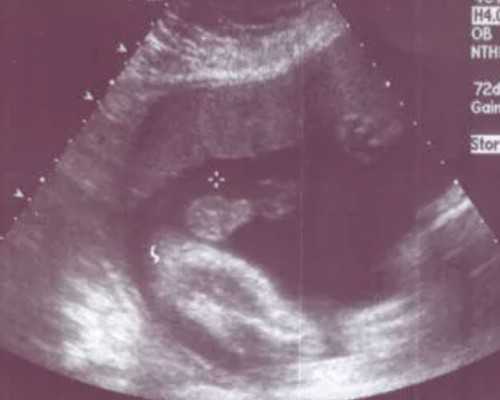

随着现在生活方式的不同和生活环境的改变,也增加了不孕不育患者的增加。这些患者为了治愈不孕不育,尝试很多办法,损失了不小的精力和财力,最后治疗的效果也不是很理想。而芜湖弋矶山医院在得到辅助生殖技术后,已经为周边不孕不育的患者带来很大的福音,不仅解决了她们的不孕不育问题,也从经济方面减少了患者的压力。那么,芜湖弋矶山医院试管婴儿技术怎么样?试管成功率高么?

芜湖弋矶山医院试管婴儿技术怎么样?芜湖弋矶山医院自从开展了辅助生殖技术以来,生殖中医把多方精力都房子了试管婴儿的项目上,攻克试管婴儿技术的种种难题,并取得了显著突破。在国家国家卫计委专家组严格评审中,弋矶山医院早就通过了试管婴儿技术,其技术和水平已经达到国家卫计委的要求,正式成为我市乃至皖江地区唯一一家经国家卫计委正式批准的进行辅助生殖技术的医疗机构。